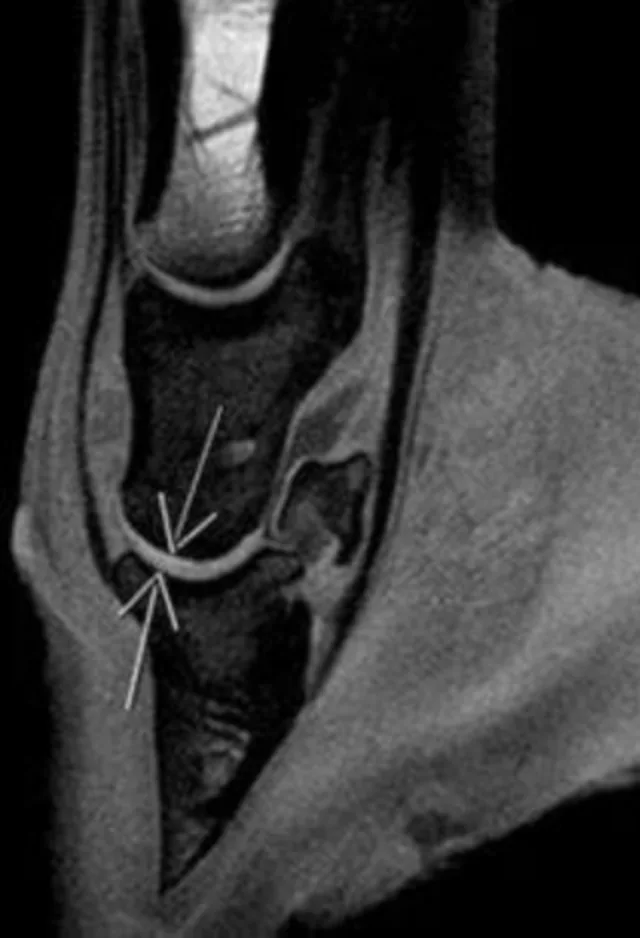

The dedicated staff and veterinarians at Oakridge Equine Hospital are leaders in Equine Medicine and Surgery. Our facilities feature state-of-the-art medical equipment including offering the first high field MRI in the central United States 20 years ago.